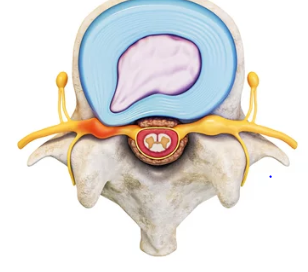

허리 디스크 원인

허리 디스크, 또는 추간판 탈출증은 많은 사람들이 겪는 통증의 원인 중 하나입니다. 이 상태는 척추 사이에 위치한 디스크가 손상되거나 변형되어 신경을 압박할 때 발생합니다. 허리 디스크의 원인은 다양하지만, 가장 흔한 원인은 다음과 같습니다.

1. 나이: 나이가 들면서 디스크의 수분이 감소하고 탄력성이 떨어져, 디스크가 쉽게 손상될 수 있습니다.

2. 부상: 낙상, 교통사고, 또는 갑작스러운 움직임으로 인한 부상이 디스크를 손상시킬 수 있습니다.

3. 과도한 체중: 과체중은 척추에 지속적인 압력을 가하여 디스크에 부담을 줄 수 있습니다.

4. 반복적인 활동: 특정 직업이나 스포츠로 인해 반복적으로 척추에 부담을 주는 활동은 디스크를 약화시킬 수 있습니다.

5. 나쁜 자세: 장시간 앉아 있거나 나쁜 자세로 일하는 것은 척추에 불균형한 압력을 가하고 디스크 문제를 유발할 수 있습니다.

이러한 원인들은 디스크의 구조에 영향을 주어 통증, 저림, 또는 근육 약화와 같은 증상을 일으킬 수 있습니다. 허리 디스크를 예방하기 위해서는 규칙적인 운동, 올바른 자세 유지, 그리고 적절한 체중 관리가 중요합니다. 만약 허리 디스크 증상이 나타난다면, 전문가의 진단과 치료를 받는 것이 필요합니다.